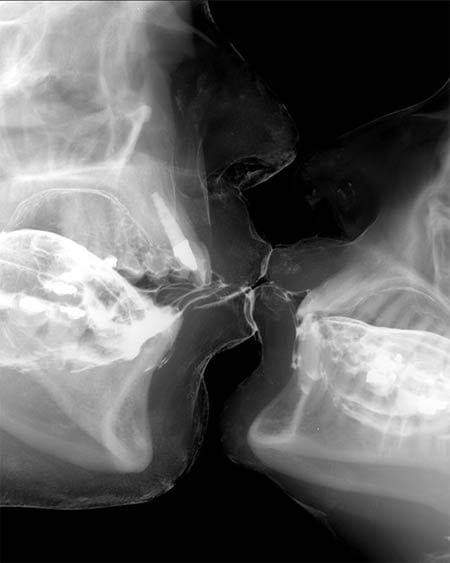

• CBCT - Cone Beam CT

CBCT predstavlja najmoderniju tehniku digitalnog snimanja Čeljusti koristeći najmoderniji software PLANMECA ROMEXIS.